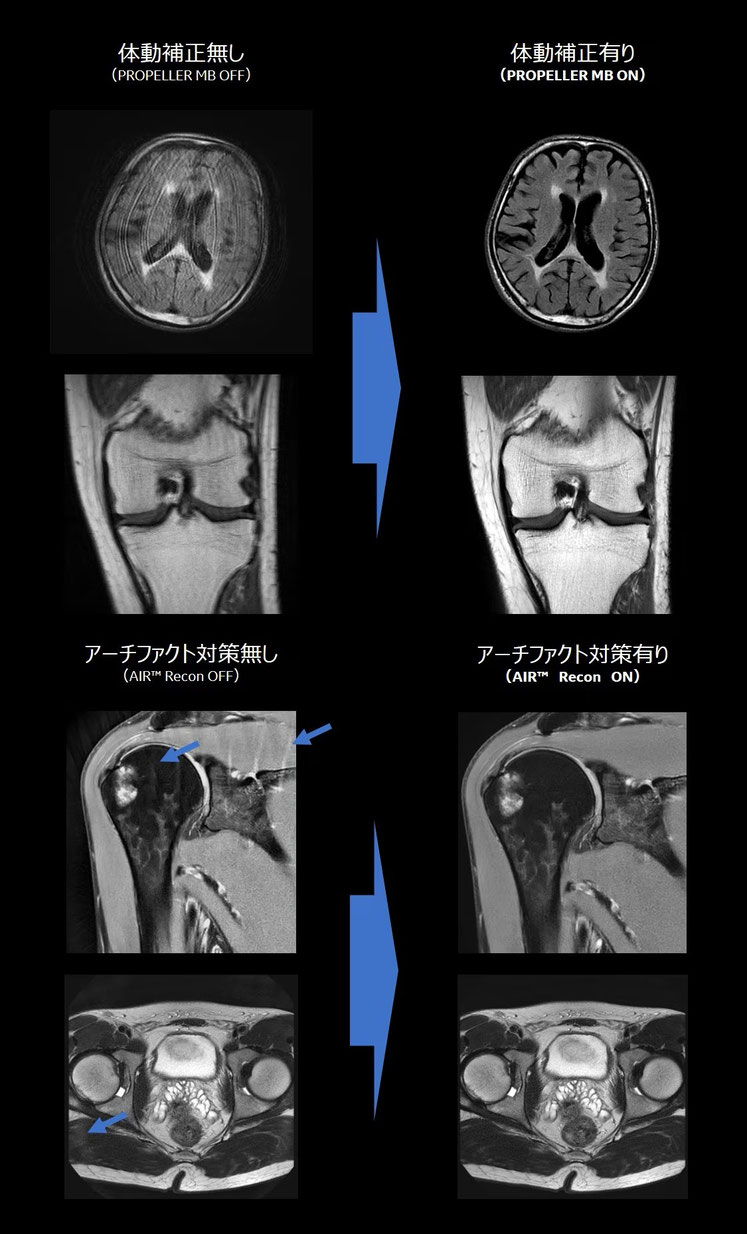

従来の検査では見えづらかった細部までより鮮明に描き出せるようになり、

各種病気を早期発見でき、適切な治療へと結びけることが出来ます。

体動 = 体の動き、無意識化での動きなど

アーチファクト = 画像のノイズや乱れなど